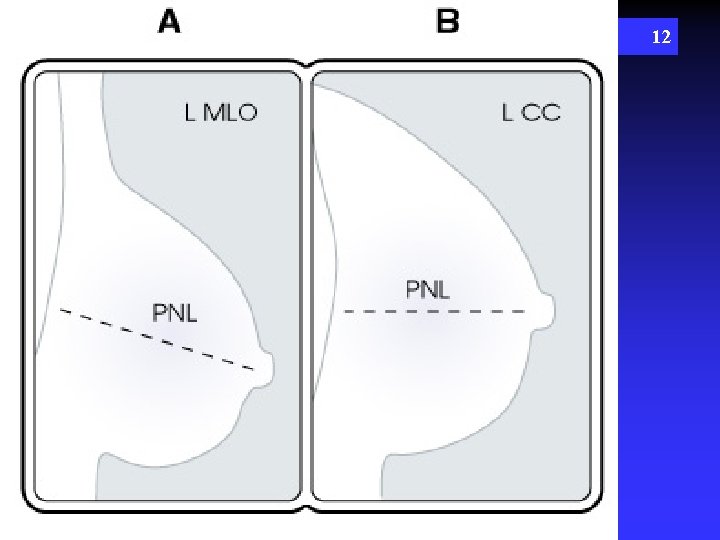

12